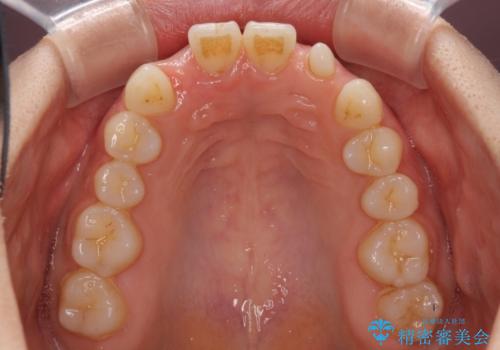

- 前歯の隙間を気にして来院された患者様です。

診察の結果、前歯が1本欠損しており、さらに矮小歯(通常よりも小さい歯)が1本存在していました。

欠損による前歯のスペースが大きかったため、事前にワイヤー矯正で前歯の位置を大きく動かし、その後は上下をインビザラインで整えることとしました。

矯正治療後には欠損部はオールセラミックブリッジに、矮小歯はオールセラミッククラウンにて補綴することとしました。

前歯のスペースは、堅い線維の通った歯肉があり、幅も大きかったことから、歯肉切除を行った上でワイヤー矯正により移動を行いました。また、上唇小帯も歯間部付近まで付着していたため、合わせて切除しました。

ワイヤー矯正により、インビザラインよりも早く、歯軸の向きもコントロールしながら移動させることができました。